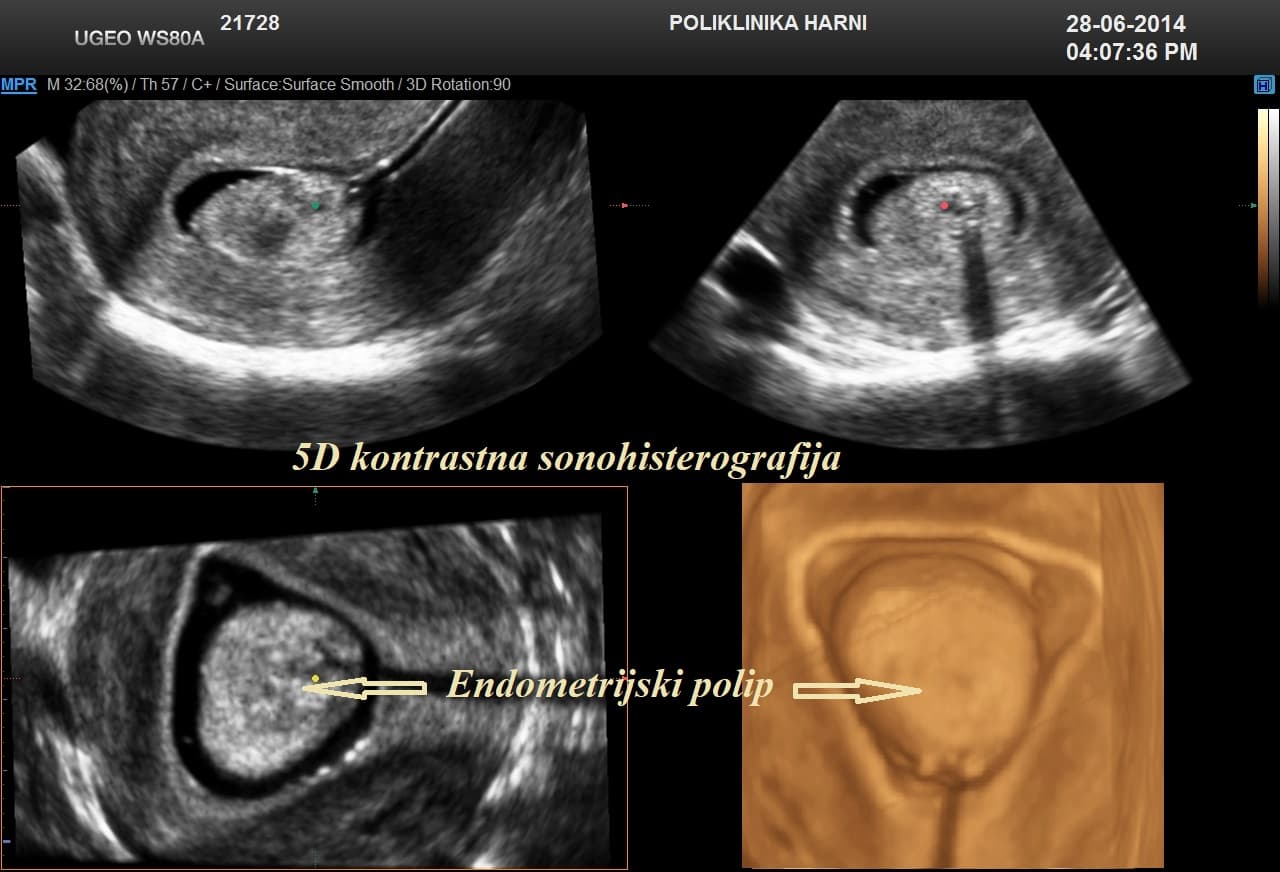

Kontrastni ultrazvukobojenim doplerom i 3D ultrazvukom / Hy-Co-Sy - hysterosalpingo-contrast-sonography sigurna je i učinkovita dijagnostička metoda u procjeni prohodnih jajovoda i od presudnog značenja u obradi neplodnih pacijentica. Provodi se u prvom dijelu menstruacijskog ciklusa nakon potpunog prestanka menstruacijskog krvarenja. Nakon pripreme pacijentice, u kanal vrata maternice se uvodi kateter i ubrizgava kontrast, a potom se prikazuju maternična šupljina, strukture unutar nje, eventualne anomalije maternice i prohodnost jajovoda. Kontraindikacije su trudnoća, krvarenje, akutna zdjelična upala i adneksalni tumor.

Pojava više-dimenzionalnog ultrazvuka omogućuje vizualizaciju ne samo određenih dijelova uterusa nedostupnih dvodimenzionalnom prikazu uslijed položaja uterusa, već i odabir optimalne ravnine kao i načina prikaza sumnjive lezije, a kod 5D ultrazvuka tehnološke inovacije omogućuju dodatne automatske presjeke koji omogućuju slojevitiju sliku i daju dubinu slici ujedno poboljšavajući dijagnostičku točnost. U dijagnostici anomalija uterusa trodimenzionalna rekonstrukcija ima prednost nad dvodimenzionalnim prikazom, te se njegova točnost može mjeriti s točnošću histerosalpingografije.

5D ultrazvučna tehnologija označuje dodatnu, vrhunsku kvalitetu revolucionarnog ultrazvučnog sustava uz automatizaciju tehnike koja više nije apsolutno ovisna o ultrasoničaru, uz najveću kvalitetu dijagnostičkog prikaza na LED monitoru i optimiziranim softverom, koji omogućuje novu slojevitu, dubinsku sliku poput CT prikaza u stvarnoj trećoj dimenziji u svim otvorenim pitanjima kako u ginekologiji, tako i opstetriciji.